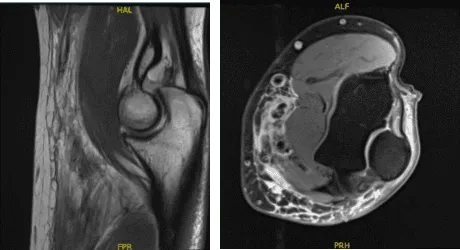

En cirugías anteriores, no reportó ninguna. Se revisó y discutió el resultado de la resonancia magnética del paciente. Los resultados mostraron rotura del tendón del bíceps y epicondilitis lateral.

Resonancia magnética 3T Codo izquierdo sin contraste